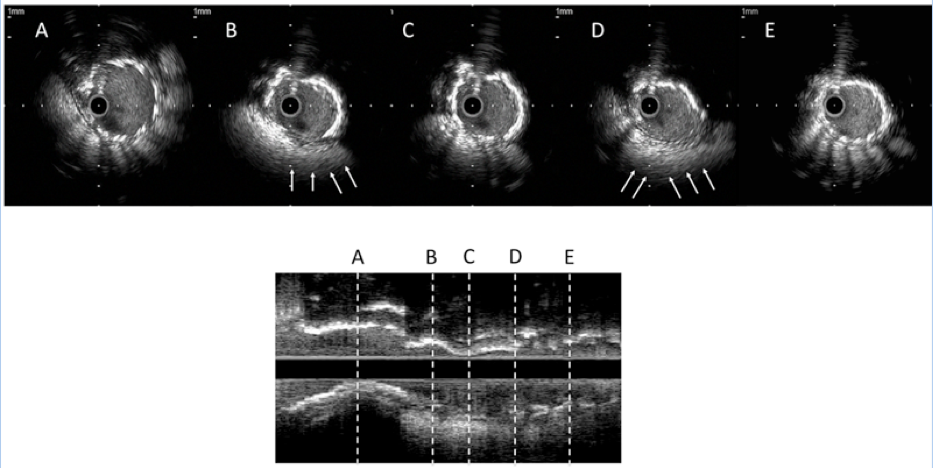

Figure 4. Intravascular ultrasound images and the longitudinal reconstruction of the right coronary artery after predilatation in case 1. Deficient struts and no acoustic shadow in panels B and D (arrows) demonstrated 2 lesions of the Nobori stent fracture (click thumbnail to view larger image).

In addition, plain fluoroscopic images revealed 2 gaps in the stent strut, suggesting SF (Figure 3B), which was then confirmed by IVUS imaging (Figure 4). We diagnosed the case as ACS due to SF, and treated the site with adjunctive stenting. After predilatation with a 3.5 × 10 mm balloon, a 3.5 × 23 mm PROMUS stent (Boston Scientific) was deployed, followed by postdilation with an excellent result (Figure 2B).